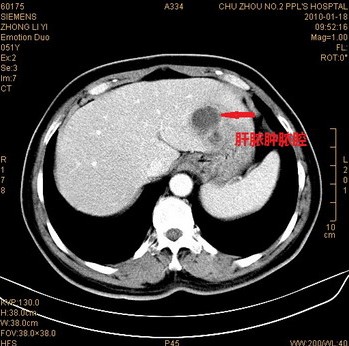

x线透视下发现有肝区阴影增大,右侧膈肌抬高,呼吸时膈肌活动范围受限的病人,结合临床表现应警惕细菌性肝脓肿,应进一步做B超、CT、MRI等影像学检查。B超、CT与MRI检查均能显示肝脏有单发或多发的低密度影,结合临床表现均能确诊。在目前诸多的辅助检查中,B超是首选的检查方法,B超检查可分辨肝内直径2cm的脓肿病灶,可以明确脓肿的多少、部位和大小,操作简便、安全、方便,且可以随时重复检查,必要时可在B超引导下进行穿刺,穿刺抽出脓液即可明确诊断又可进行细菌培养、药敏实验,选择有效抗菌药物。

根据病史,临床表现,以及B超和X线检查,即可诊断本病。必要时可在肝区压痛最剧烈处或超声引导下行诊断学穿刺,抽出脓液即可证实本病。

肝脏肿的临床诊断基本要点为:①右上腹痛、发热、肝脏肿大和压痛;②X线检查右侧膈肌抬高、运动减弱;③超声波检查显示肝区液平段。若肝穿刺获得典型的脓液,或脓液中找到阿米巴滋养体,或对特异性抗阿米巴药物治疗有良好效应即可确诊为阿米巴性肝脓肿。